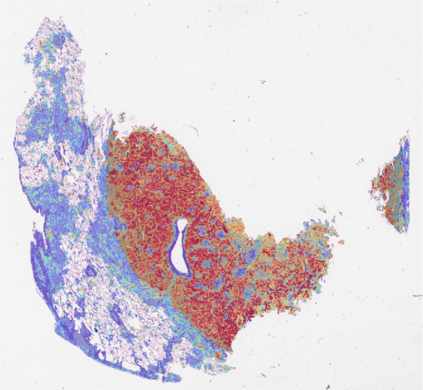

Multiple instance learning (MIL) is a powerful approach to classify whole slide images (WSIs) for diagnostic pathology. A fundamental challenge of MIL on WSI classification is to discover the \textit{critical instances} that trigger the bag label. However, previous methods are primarily designed under the independent and identical distribution hypothesis (\textit{i.i.d}), ignoring either the correlations between instances or heterogeneity of tumours. In this paper, we propose a novel multiplex-detection-based multiple instance learning (MDMIL) to tackle the issues above. Specifically, MDMIL is constructed by the internal query generation module (IQGM) and the multiplex detection module (MDM) and assisted by the memory-based contrastive loss during training. Firstly, IQGM gives the probability of instances and generates the internal query (IQ) for the subsequent MDM by aggregating highly reliable features after the distribution analysis. Secondly, the multiplex-detection cross-attention (MDCA) and multi-head self-attention (MHSA) in MDM cooperate to generate the final representations for the WSI. In this process, the IQ and trainable variational query (VQ) successfully build up the connections between instances and significantly improve the model's robustness toward heterogeneous tumours. At last, to further enforce constraints in the feature space and stabilize the training process, we adopt a memory-based contrastive loss, which is practicable for WSI classification even with a single sample as input in each iteration. We conduct experiments on three computational pathology datasets, e.g., CAMELYON16, TCGA-NSCLC, and TCGA-RCC datasets. The superior accuracy and AUC demonstrate the superiority of our proposed MDMIL over other state-of-the-art methods.